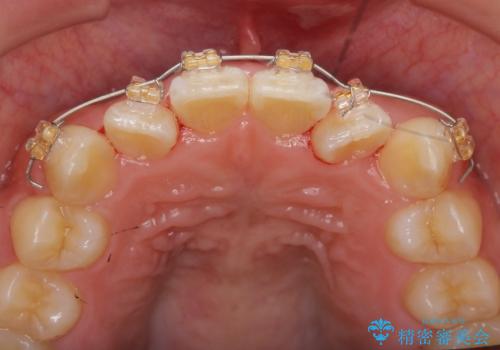

- ねじれの目立つ前歯を改善したいと、矯正治療を希望され来院されました。

インビザラインの不得意な上顎前歯のねじれの改善を、マウスピース矯正を行う前に前歯のみの部分ワイヤー矯正を行うことで治療期間の短期化を目指します。

上顎前歯のねじれはマウスピースで治りづらいため、マウスピース矯正の治療期間の長期化をきたしやすい歯列不正です。

マススピース矯正を始める前に、部分ワイヤー矯正を行うことで治療の短期間化・良好な仕上がりを達成することができました。